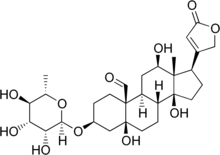

β-Antiarin | |

| IUPAC names

α-Antiarin: (3S,5S,8R,9S,10S,12R,13S,14S,17R)-5,12,14-trihydroxy-13-methyl-17-(5-oxo-2H-furan-3-yl)-3-[(2R,3R,4R,5R,6R)-3,4,5-trihydroxy-6-methyloxan-2-yl]oxy-2,3,4,6,7,8,9,11,12,15,16,17-dodecahydro-1H-cyclopenta[a]phenanthrene-10-carbaldehyde β-Antiarin: (3S,5S,8R,9S,10S,12R,13S,14S,17R)-5,12,14-trihydroxy-13-methyl-17-(5-oxo-2H-furan-3-yl)-3-[(2R,3R,4R,5R,6S)-3,4,5-trihydroxy-6-methyloxan-2-yl]oxy-2,3,4,6,7,8,9,11,12,15,16,17-dodecahydro-1H-cyclopenta[a]phenanthrene-10-carbaldehyde | |

| C29H42O11 | |

| Molar mass | 566.644 g·mol−1 |

Antiarins are cardiac glycoside poisons produced by the upas tree (Antiaris toxicaria).[2] There are two forms, α-antiarin and β-antiarin.

β-Antiarin

β-Antiarin, a cardiac glycoside steroid, can be isolated from upas tree latex (Antiaris toxicaria). Its use ranges from medical use, such as hypertension treatment, to arrow poison application. It also proves to be more poisonous than curare, sporting a low LD50 of 0.1 mg/kg in most mammals.[3]

To date, β-antiarin has only been isolated from the upas tree by the scientist H. Kiliani in 1896; no synthetic synthesis has yet been achieved.[4]